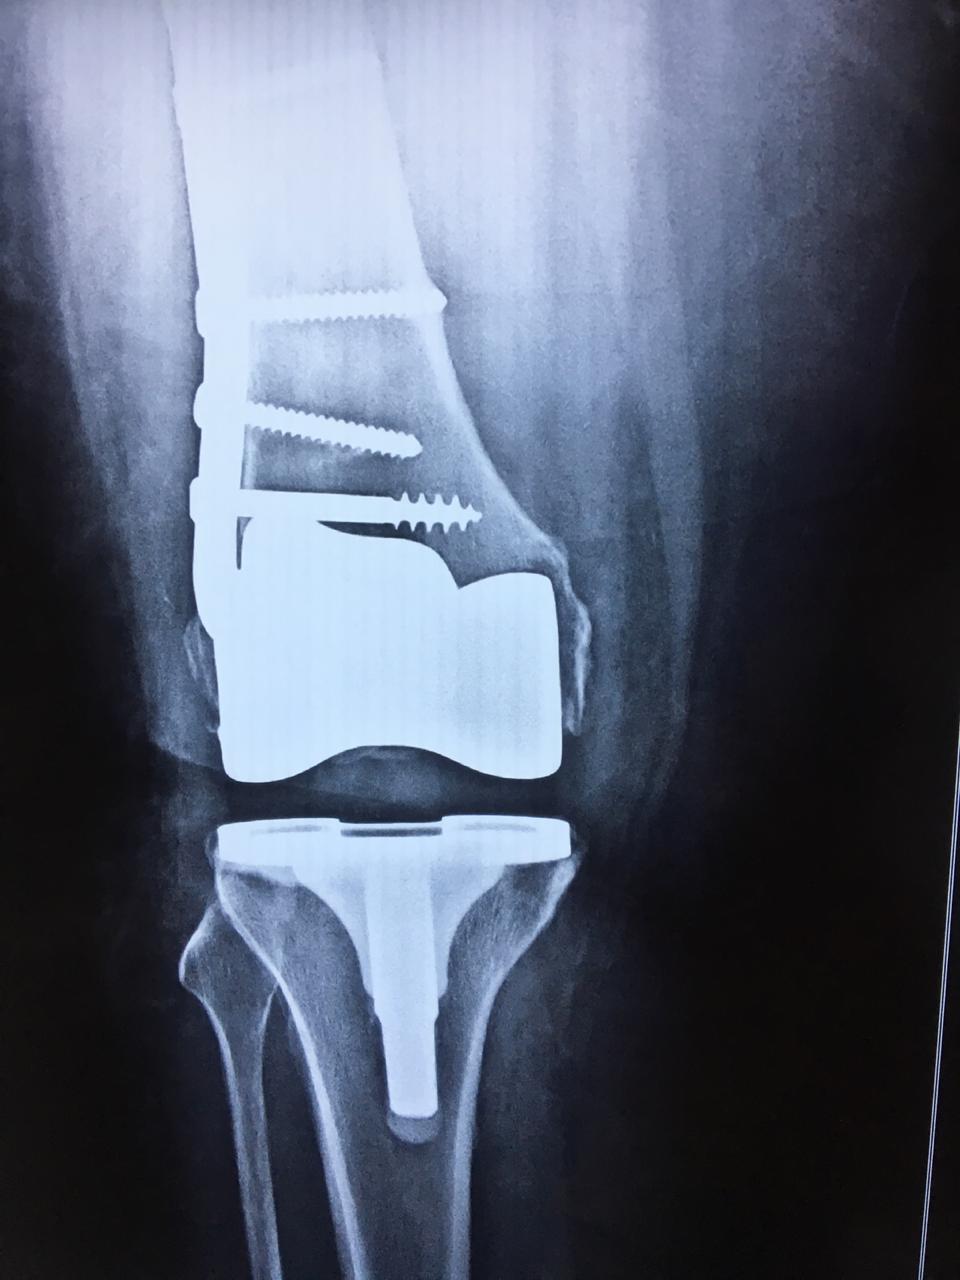

Total Knee Replacement with Fracture Plate Metal Plate In Knee Surgery Pressure may be exerted on the flat of the foot), and the newly altered bone is secured with metal plates and screws. The lower end of the femur. You can expect some pain and swelling around the cut (incision) the doctor made. But it's common to have some pain for up to several weeks. The bone at the osteotomy wound. Metal Plate In Knee Surgery.

Knee Replacement, for a failed Knee fracture surgery (plates and screws Metal Plate In Knee Surgery Thinking about a total knee replacement? Implants are made of metal alloys, ceramic material, and strong plastic parts. It’s also known as open reduction and internal fixation. The replacement knee joint is comprised of a flat metal plate and stem implanted in your tibia, a polyethylene bearing surface and a contoured. But it's common to have some pain for up. Metal Plate In Knee Surgery.